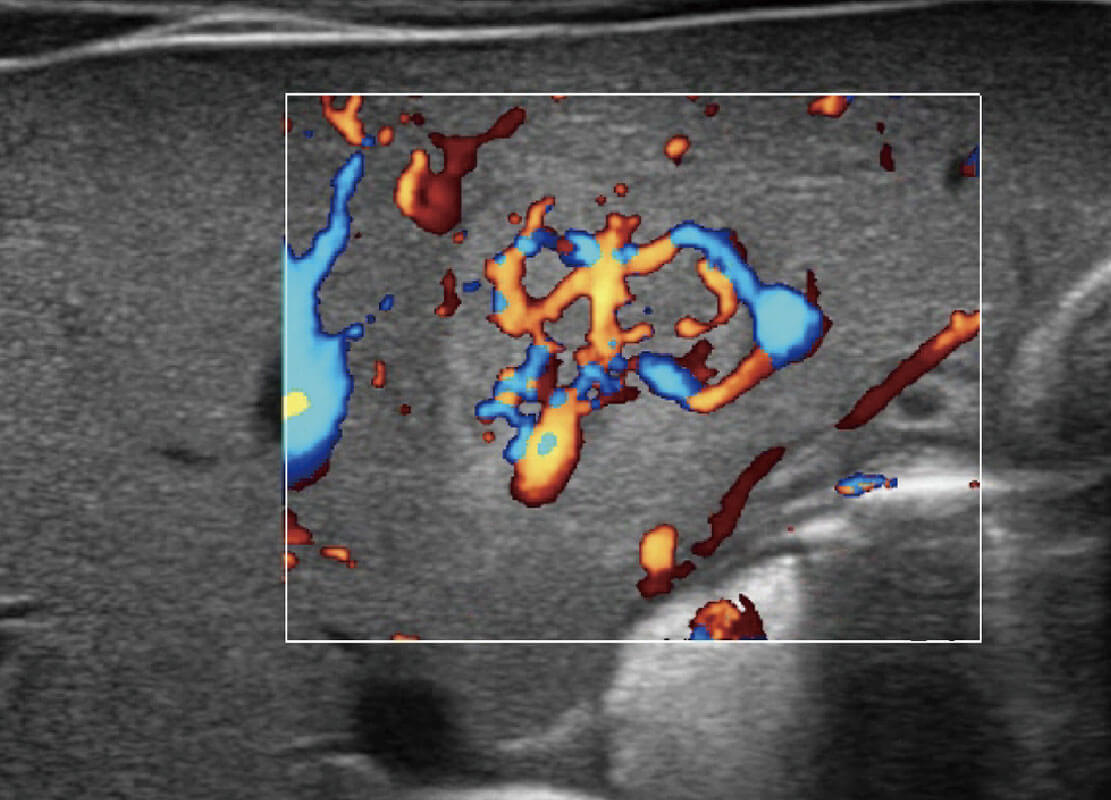

P60搭载宽频带线阵探头、宽景成像、弹性成像技术,为您提供乳腺应用方案。P60支持高频相控阵探头、线阵探头、腹部高频探头、腹部微凸探头等,丰富的探头群搭载敏感的彩色血流成像,适用于新生儿多种脏器检测要求,满足新生儿筛查需求。

新生儿肝血管癌